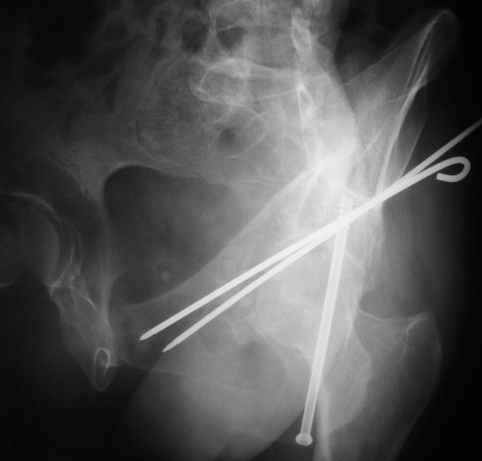

Женя! Класный перелом. Отлично репонируется изнутри таза, но лучше фиксированть сзади. Классический перелом для двустороннего доступа.

Однако есть альтернатива. Репозиция из подвздошного доступа тазовыми щипцами с разнодлинными браншами или тазовым пистолетом, а фиксация задней колонны через седалищный бугор или тазрвыми винтами 4,5 или каннюлированными 6,5 или 7,3. По-моему я посылал на ортофорум такой снимок, когда жаловался на ишемический неврит седалищного нерва через сутки после операции. Не забудь про шейку бедра - мне кажется будет хорош длинный PFN любой фирмы, какую ты найдешь, а нет так UFN + miss a nail, как это здорово делают мои земляки - Ебурбуки. Пока.